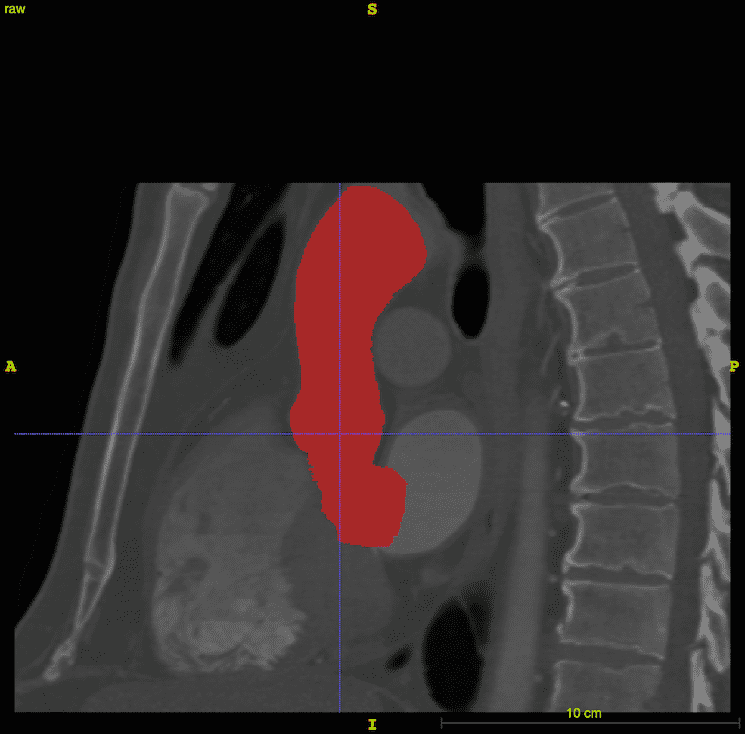

The aortic root and ascending aorta were segmented by a semi-automated method implemented in the ITK-SNAP software. ITK-SNAP [43, 44], which is based on the Insight Segmentation and Registration Toolkit (ITK) [45, 46], provides a graphical interface for the implementation of the active contour model, also known as Kass snakes [47], for semi-automatic segmentation. The algorithm works by minimizing an energy functional that is determined by voxel intensities. The generated segmentation is shown in Fig. 2.

A three-dimensional representation of the aortic root and ascending aorta was generated from publicly available medical image data. This study uses one of the sample data sets from the OsiriX DICOM Image Library that consists of three-dimensional computed tomography angiography (CTA) of an anonymous patient’s chest following administration of a contrast agent. The use of a contrast agent enables better discrimination of the blood vessels and heart chambers than non-contrast CT images. The image data were acquired at the Ronald Reagan University of California at Los Angeles Medical Center in Santa Monica, CA using a Siemens SOMATOM Sensation 16 CT scanner. The image resolution is 512512355 with a voxel size of 0.470.470.5 mm. The image was processed by an anisotropic diffusion filter to mitigate noise. Sample renderings of the patient data are shown in Fig. 1.

Several distinct software applications are used to construct the full model. The construction pipeline starts with three-dimensional NRRD (nearly raw raster data) files containing the medical image data. Segmentation and initial geometry construction is generated using ITK-SNAP. Further adjustments are made in SOLIDWORKS (Dassault Systèmes SOLIDWORKS Corporation, Waltham, MA, USA) to fix any irregularities. SOLIDWORKS is also used to generate the geometry of the aortic valve leaflets. The STL (STereoLithography) geometry constructed in SOLIDWORKS is then used in Bolt (Computational Simulation Software, LLC, American Fork, UT, USA) to construct a hexahedral mesh for the aortic root. Placement of the model valve leaflets within the aortic root is finalized in Trelis (Computational Simulation Software, LLC, American Fork, UT, USA), which is a mesh generation software application based on CUBIT from Sandia National Laboratory. Trelis is also used to generate tetrahedral meshes of the aortic valve leaflets. Because the leaflets and vessel wall are both modeled using the IB method, it is not necessary to use conforming discretizations of the leaflets and wall, which greatly simplifies the mesh generation process. The overall model construction workflow is detailed in Algorithm 1. The inflow section of the model is truncated at the left ventricular outflow tract, and the outflow section of the model is truncated in the aortic arch before the first bifurcation. In the FSI simulation, the inflow and outflow sections are coupled to reduced-order models that provide driving and loading conditions, and that establish realistic pressure differences across the model vessel.